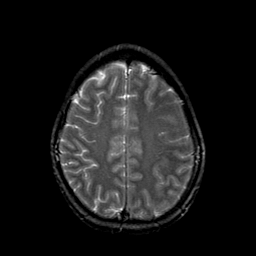

Metastatic bronchogenic carcinoma: T2-weighted MR -- Slice #17

[Home][Help][Clinical] Slice 17